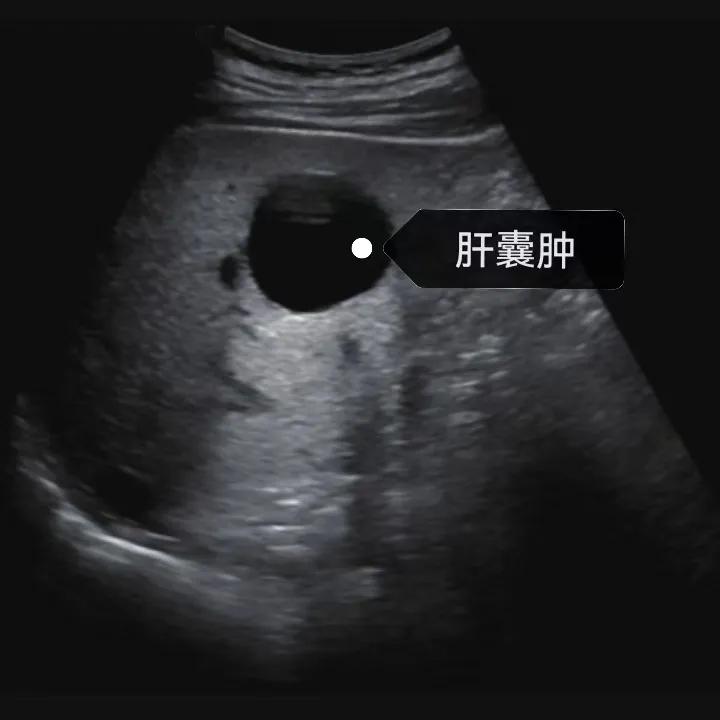

漯河市中醫(yī)院健康科普:認識肝囊腫

隨著人們健康意識的提升,越來越多的人每年會進行健康體檢,由于腹部(肝膽胰脾)超聲作為常規(guī)體檢項目之一, 肝囊腫的檢出率也愈發(fā)升高,大部分人對“腫”字都比較困惑,今天我們就來一起了解一下肝囊腫。

肝囊腫是一種常見的肝臟良性疾病,呈圓形或橢圓形,外由上皮細胞包裹形成包膜,內由清亮、無色、無細胞成分的囊液填充,看上去就像是一顆注滿了水的氣球,因此通俗一點說就是肝臟中的“水泡”。

04、如何發(fā)現(xiàn)肝囊腫

超聲通常是診斷肝囊腫的首選方法,彩超對肝囊腫的檢出率可達98%,<1cm的囊腫也可檢出。肝囊腫常表現(xiàn)為圓形或橢圓形無回聲,包膜光滑完整,邊界清晰,可有側壁回聲失落征象,后方回聲增強。病程長、囊腫較大者或囊內有過出血、感染者,無回聲腔內可見少量絮狀回聲漂浮。超聲對肝囊腫的診斷準確而靈敏,且方法簡單、無創(chuàng)、費用低、可重復性高,因此常常被作為首選。